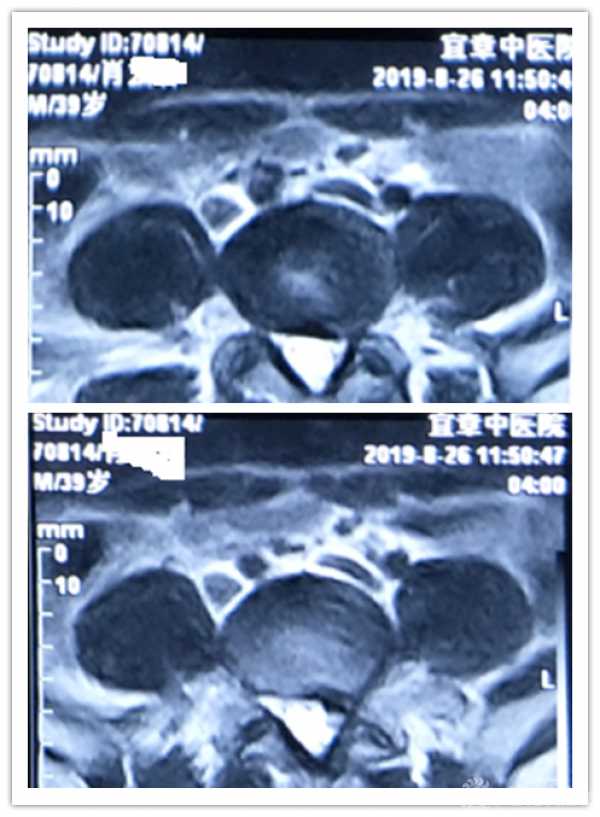

MRI、CT影像学表现:

既往体健。专科情况:L4/5稍有压痛,左臀部致左下肢伴有明显放射胀痛感,以左小腿前外侧为明显;左侧直腿抬高试验(+),左侧踇背伸肌肌力IV级,左下肢伴有明显跛行,左侧膝反射减弱,余(-)。

病程:腰痛伴左下肢放射痛5年,加重5天入院,入院诊断:L4/5椎间盘脱出伴坐骨神经痛。